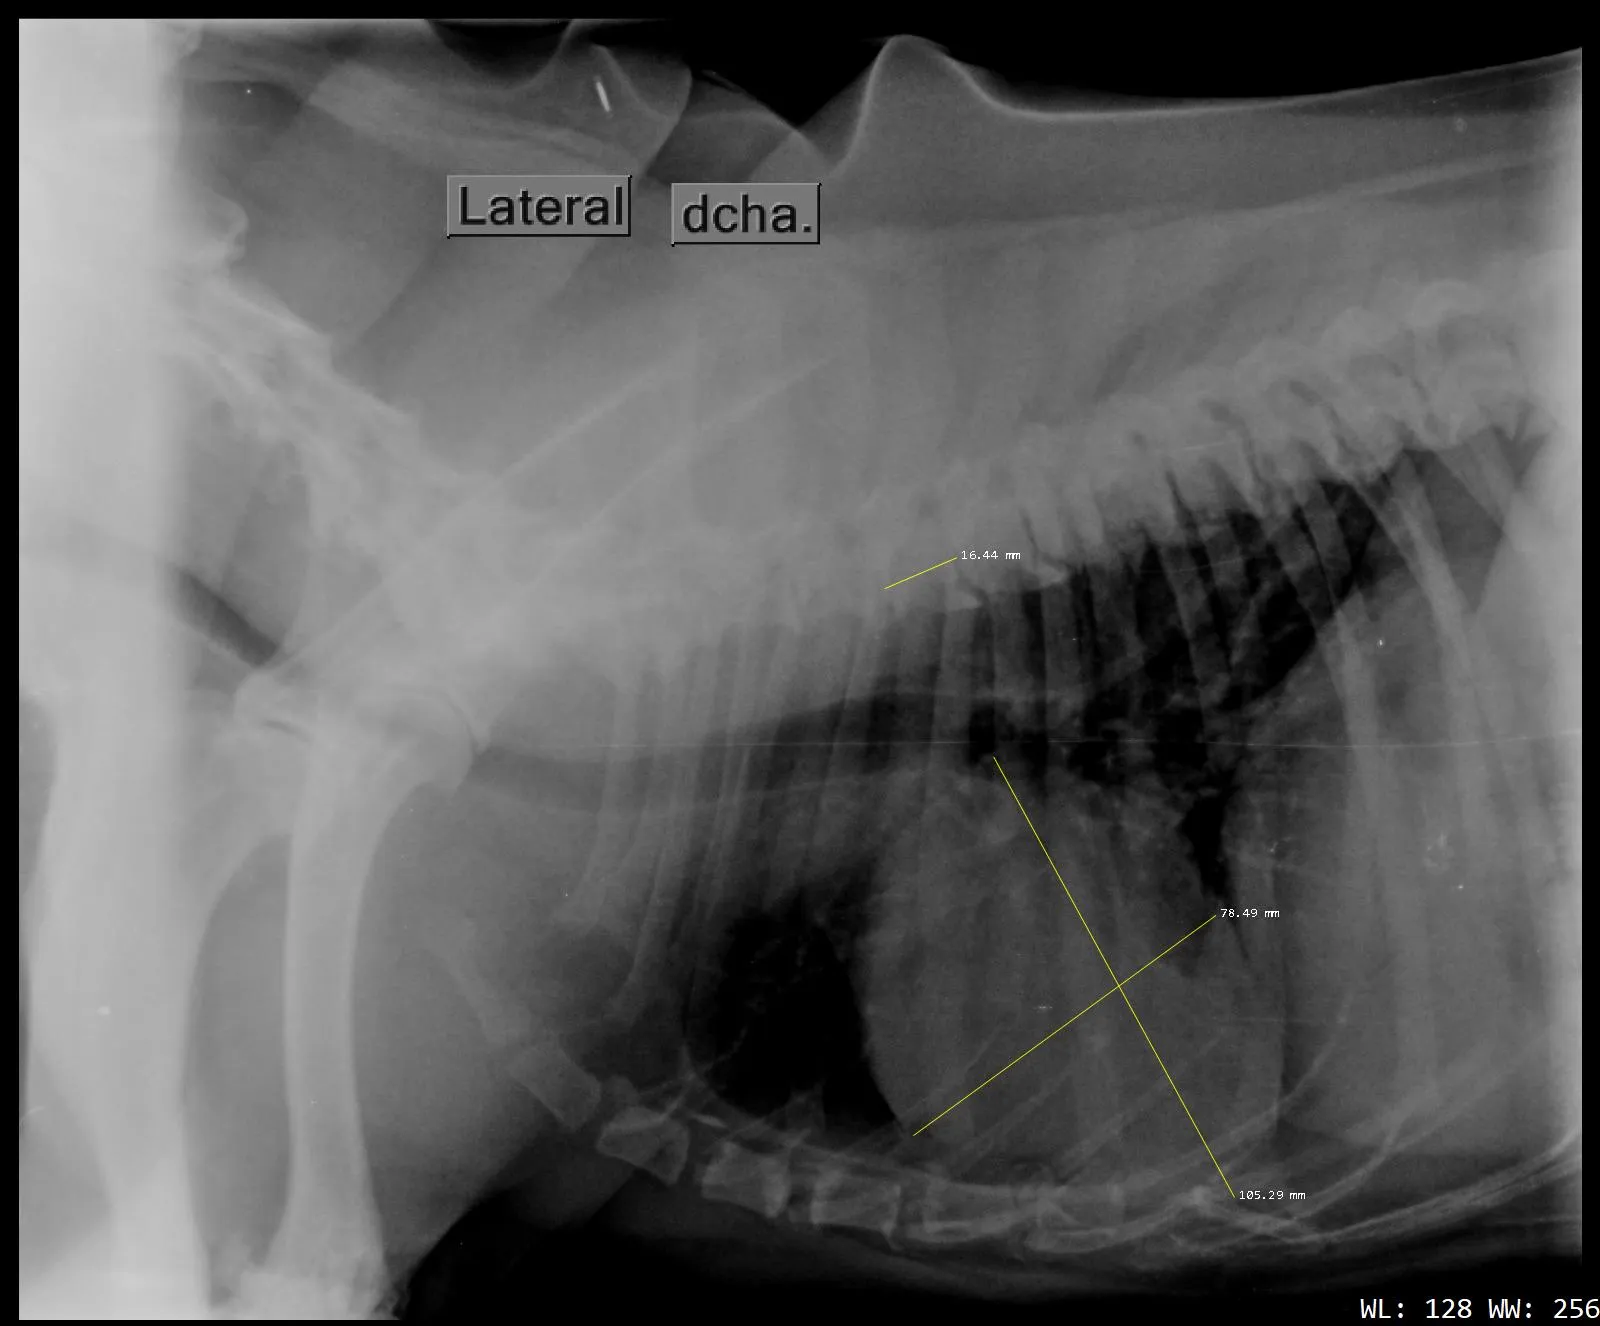

Cardiología Especializada

Diagnóstico y tratamiento de enfermedades cardíacas para asegurar una vida larga y saludable a tu mascota.

Ecografía y Eco-doppler

Tecnología de ultrasonido avanzada para un diagnóstico por imagen preciso y no invasivo.